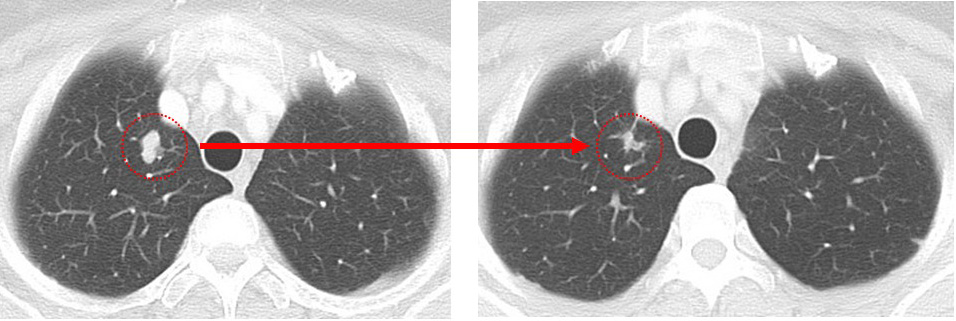

先日MRIをしました所、肝臓は何ともなく、たまたま映った左肺に1箇所腫瘤があったとのことで、造形剤なしのCTを急遽追加でし、同じように左肺に1.3cmの腫瘤が確認されました。

1.肺病変を「転移なのか?の確定診断目的+(局所療法としての)切除目的+(転移ならば)サブタイプを確認する目的」で(胸腔鏡下に)切除⇒その後全身療法

2.まずは全身療法(やはりfirst line はsacituzumab govitecanとなるでしょう)

⇒(肺病変が)消失しないのであれば「ここで」肺の手術

上記1,2どちらにせよ、まずは「画像上完全緩解cCR」 それをどの位維持できるか? この維持が10年を超えた時、それは根治の可能性を秘めてきます。

肺 かなり効いている

肺転移は(分子標的薬だけで)コントロールされている。

①「多発肺転移」は画像上かなり小さくなっているのに「胸の腫瘍は小さくならない」

anthracyclin終了時の時点でのCTでcCR

病変が(少なくとも)画像上消失した状態。